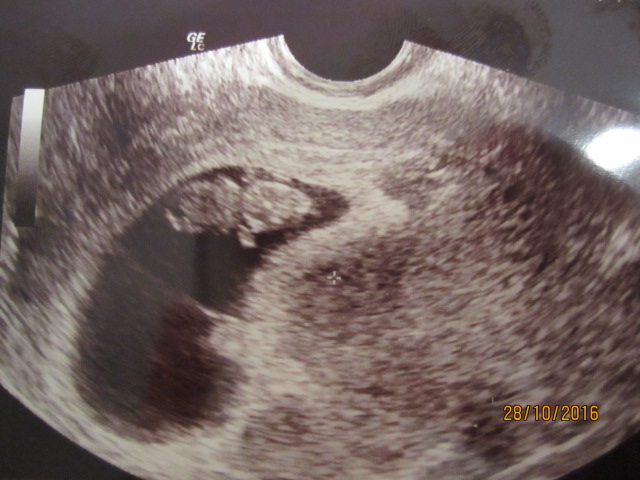

On. Tänään aamulla oli (toinen) varhaisultra, rv 8+2. Pelotti niin että oksennus oli tulla! Ensimmäinen ultra oli rv 6+4 ja silloin näkyi pieni katkarapu ja tykyttävä sydän. Sain uuden ajan siitä kahden viikon päähän eli tälle aamulle. Siellä meidän 2cm pitkä ihanuus heilutteli käsiä ja jalkoja sekä sydän sykki. Uskomatonta että 2cm kokoisella ihmisen alulla voi olla jo raajat joita se heiluttelee :eek: Tää maailma on kyllä ihmeellinen paikka!! Nyt olen luvannut itselleni lopettaa jossittelun ja alkaa nauttimaan tästä tilasta. Kaiken jälkeen meille on kuin onkin tulossa vauva :Heartred Toivottavasti kukaan ei pahastu kuvasta :oops: Ajatuksena on " kaikki on mahdollista" vaikka välillä muulta tuntuukin!!

IMG_4259.JPG